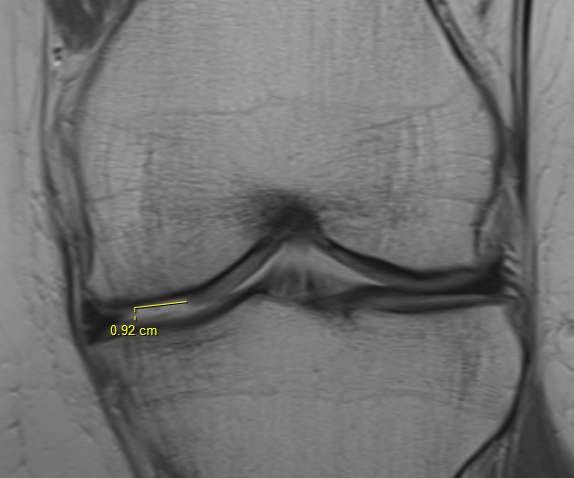

Grade 2: Partial thickness defect < 1.5 cm in diameter

Grade 3: Fissuring to subchondral bone, > 1.5 cm in diameter

Sizing

3 or 5mm graduated probe

- measure in 2 dimensions

- give a size in cm2

- assumes that lesions are basically rectangular

- tend to overestimate size arthroscopically